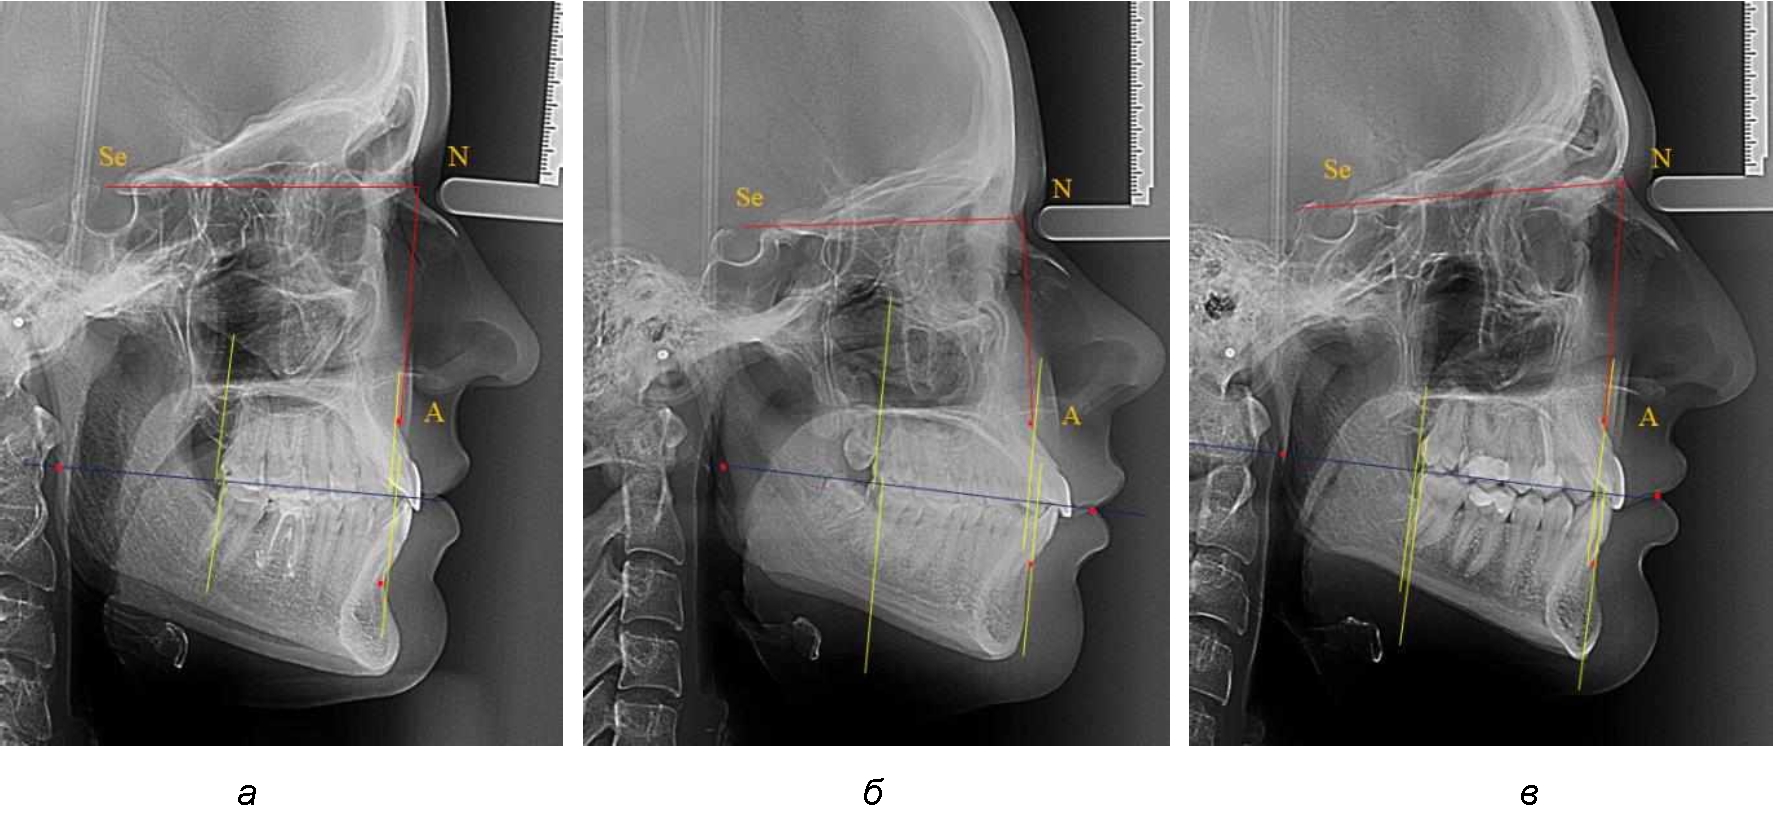

Аналогичное расстояние было отмечено и при расположении дистальных окклюзионных точек верхней и нижней челюсти (рис. 2).

Рис. 2. Положение апикальных точек и челюстей при нормопозиции (а), антепозиции (б) и ретропозиции (в) верхней челюсти

При анализе рентгенограмм, было отмечено, что на 26 снимках из 58 [(44,83 ± 6,53) %] отмечалась нормопозиция верхней челюсти. При этом средняя величина лицевого угла (ANSe) составила (85,04 ± 0,56)°, и пациенты были отнесены к 1-й группе 1-й подгруппе. Антепозиция верхней челюсти была отмечена на 20 те-лерентгенограммах [(34,483 ± 6,24) %], при этом величина лицевого угла составляла (89,12 ± 0,62)°. Ретропозиция была отмечена на 12 рентгенограммах [(20,69 ± 5,32) %], а средняя величина лицевого угла составляла (80,21 ± 0,48)°.

При всех вариантах положения верхней челюсти, было отмечено, что альвеолярно-денталь-ные размеры верхних зубо-челюстных дуг были близки по значению к аналогичным размерам нижней челюсти и разница в размерах не превышала 1,0–1,5 мм, а средняя величина различия показателей составляла (1,07 ± 0,54) мм.

Расстояние от конструируемой точки окклюзионной плоскости на ветви челюсти («rmРOcP») до апикальных точек Downs на обеих челюстях также коррелировало между собой, и средняя величина различия показателей составляла (1,23 ± 0,69) мм. Проекция нижней апикальной точки на окклюзионную линию, как правило, располагалась несколько кпереди проекции верхней апикальной точки, на величину около 1 мм, что соответствовало оптимальным данным Wits-анализа.